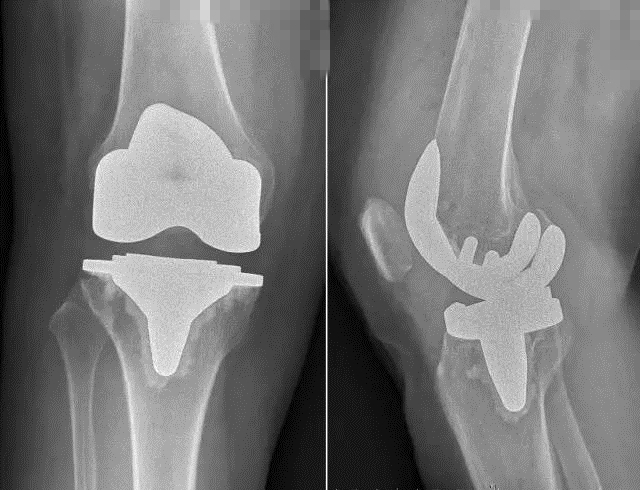

疗效改善的同时,新型假体对手术精准度的要求也提高了,为此,蔡谞教授和关节中心团队做了充足的准备,术前对手术参与人员进行了严格的操作训练。手术全程1个小时左右顺利结束,术后影像显示,新型假体安放位置精确,患者术后第2天即开始下床进行功能锻炼,术后7天顺利出院。(编辑 韩冬野

术后患者膝关节平片